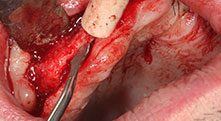

Bratu: Utilizamos los insertos de forma rutinaria para la extracción de injertos óseos y la ranuración de las crestas alveolares. También utilizamos las Piezomed B6/B7 para practicar osteotomías en dientes retenidos y no retiramos implantes que pueden conservarse. Todas estas son indicaciones que requieren cortes profundos y limpios.

¿Podría describirnos brevemente cómo procede, por ejemplo, a la hora de mover injertos óseos destinados a trasplantes?

Bratu: Preferimos realizar las osteotomías en la línea oblicua externa de la cara posterior del maxilar inferior, y no en la región situada entre los orificios. Tras realizar una incisión en los tejidos blandos, utilizamos las nuevas sierras para definir el contorno de la osteotomía. De este modo, conseguimos una preparación completa en prácticamente el 80 por ciento de los casos. Por otro lado, en algunas ocasiones también utilizamos otros insertos piezoquirúrgicos, así como un cincel para mover el injerto. Para nosotros, esta es una técnica de intervención muy eficaz.